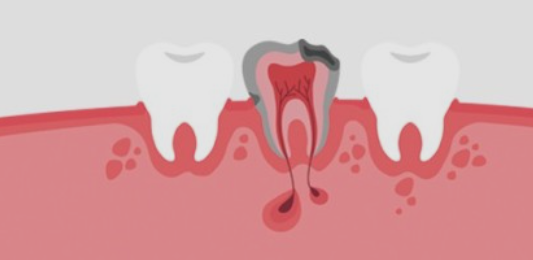

외상 또는 충치로 인해 치아의 치수(신경)가 손상되었거나 염증이 생기게되면 통증이 느껴지게 되요. 문제가 생긴 신경을 방치하게 되면 일상생활에 지장이 있을 정도로 통증이 심해지며 염증이 점점 커지기 때문에 손상되었거나 염증이 생긴 치수를 제거하는 것이 치아 신경치료이에요.

2) 뿌리 끝 염증으로 나타나는 통증

치아 신경치료 후 뿌리 끝에 염증이 생기며 통증이 나타나는 경우도 있어요. 신경치료가 잘 되었음에도 뿌리끝에 염증이 생기는 경우가 있는데요, 이는 복잡한 구조로 제거할 수 없는 근관속 염증이 뿌리끝에 모이게 되면서 잇몸이 부었다 가라앉았다를 반복하는 경우, 통증이 생기는 경우 등의 증상이 생기게 되며 치료방법으로는 치아 재식술 or 임플란트를 통해 치아의 기능을 회복하기도 해요.